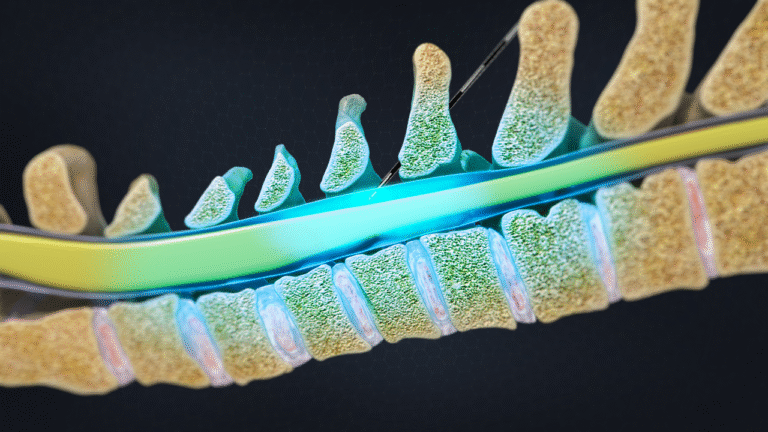

- Minimally invasive procedures

- Neuromodulation